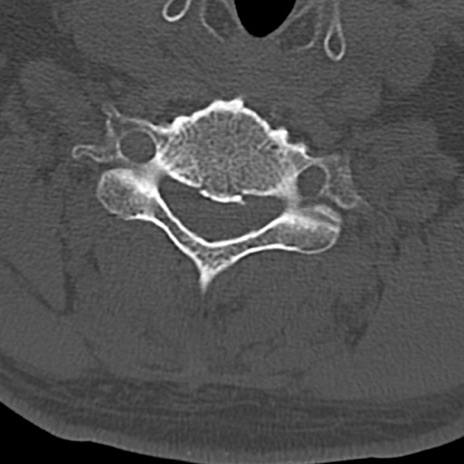

頚椎CT

横断像